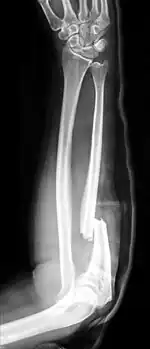

| Midshaft fracture of the radius and ulna | |